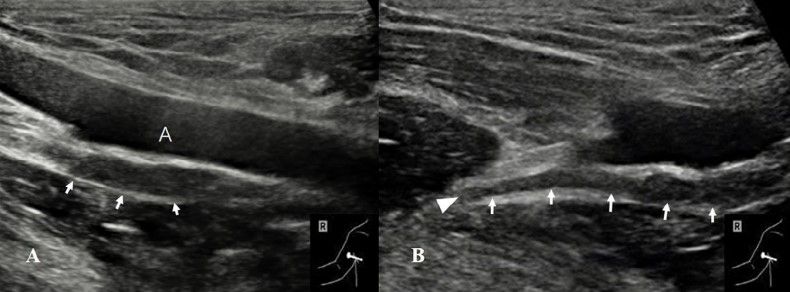

病例1:患者34岁男性,右肩受伤,活动范围受限,持续2个月。A,左侧腋神经(箭头)正常。B,与正常侧相比,右侧腋神经(箭头)回声减低,弥漫性肿胀。

病例3:21岁女性右肩关节向前脱位。A,腋神经(箭头)位于腋动脉(A)的后方,明显增厚。B,神经完全断裂,断端挛缩(箭头)。